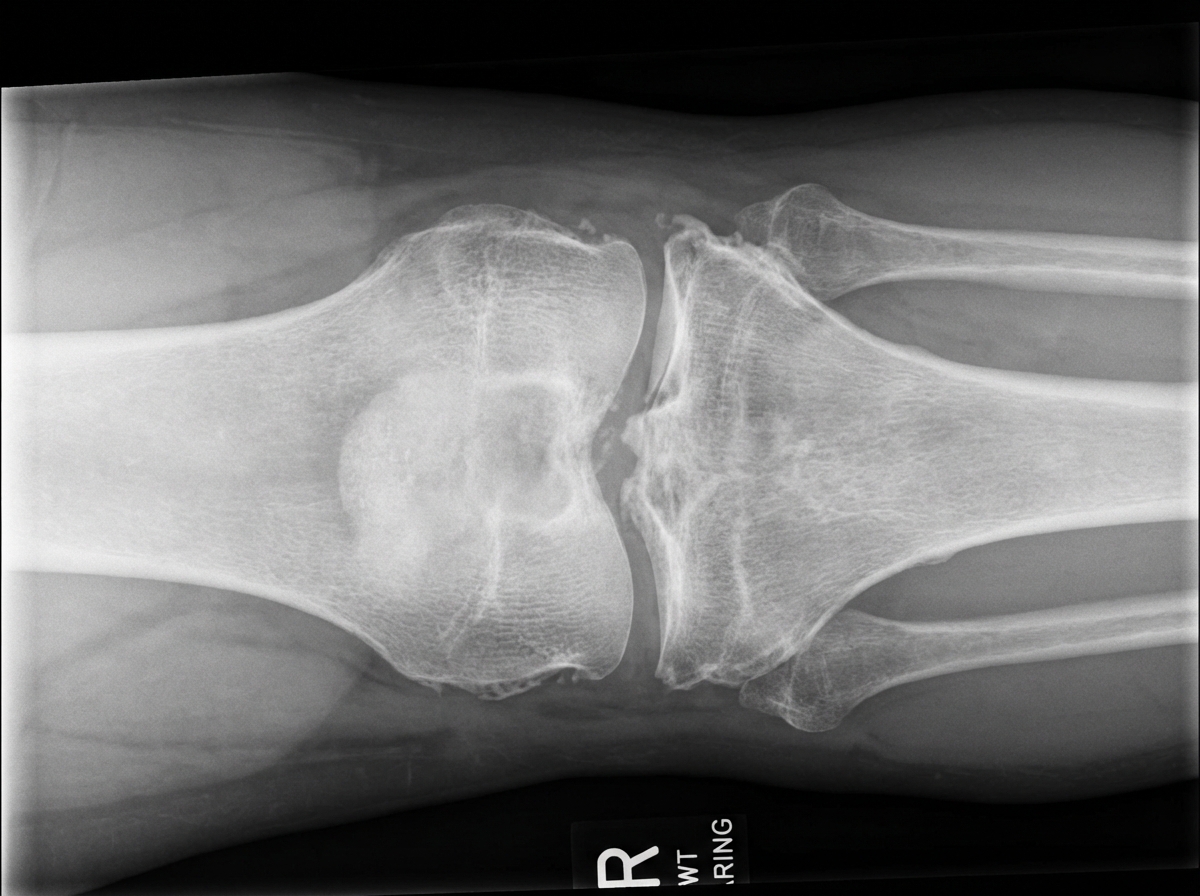

A 52-year-old woman comes to the physician because of a 3-week history of pain in her right knee. The pain is worse at the end of the day and when she walks. She says that it has become difficult for her to walk up the flight of stairs to reach her apartment. She has hypertension and psoriasis. Her sister has rheumatoid arthritis. She drinks 2–3 beers daily. Current medications include hydrochlorothiazide, topical betamethasone, and a multivitamin. She is 160 cm (5 ft 3 in) tall and weighs 92 kg (202 lb); BMI is 36 kg/m2. She appears anxious. Her temperature is 37°C (98.6°F), pulse is 87/min, and blood pressure is 135/83 mm Hg. Cardiopulmonary examinations shows no abnormalities. There are several scaly plaques over the patient's upper and lower extremities. The right knee is not tender nor erythematous; range of motion is limited. Crepitus is heard on flexion and extension of the knee. Her hemoglobin concentration is 12.6 g/dL, leukocyte count is 9,000/mm3, and erythrocyte sedimentation rate is 16 mm/h. An x-ray of the right knee is shown. Which of the following is the most appropriate next step in the management of this patient?